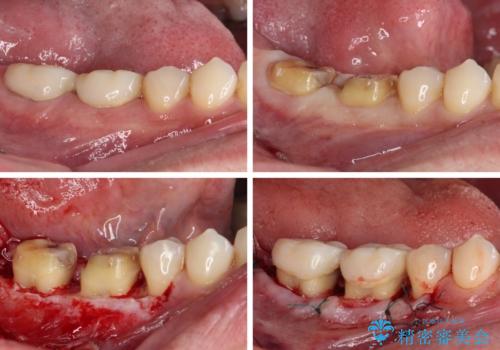

奥歯の歯間部の歯肉が炎症で赤黒くなっており、歯周ポケットを検査したところ、6-8mm(正常では3mm以下)であり、外科処置が適用となる状態でした。

まずは仮歯に置き換え、歯周ポケットを除去するための外科処置(歯肉弁根尖側移動術)を行い、治癒を待ってセラミッククラウンにて補綴治療を行うこととしました。

外科処置後は知覚過敏症状が酷くなることが多いのですが、術後は比較的落ち着いており、スムーズに処置を進めることができました。